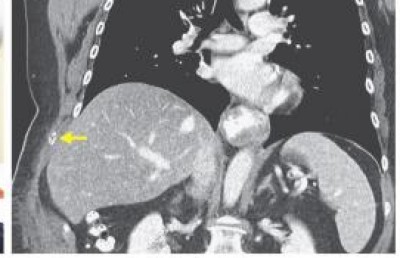

އެމެރިކާގެ މެސަޗޫސެޓްސްގައި ދިރިއުޅޭ މި އަންހެންމީހާގެ ސީޓީ ސްކޭން ހަދަން ޑޮކްޓަރު އެންގީ އޭނާގެ މެޔާއި ބަނޑުގައި ކަޅުވެފައި ހުރި ތަން ފެނިގެންނެވެ. ސީޓީ ސްކޭން އިން ދެއްކި ގޮތުގައި އަންހެންމީހާގެ މޭ ކަށިގަނޑެއް ބިނދި އެއްކޮށް އޮތީ ވަކިވެފަ އެވެ.